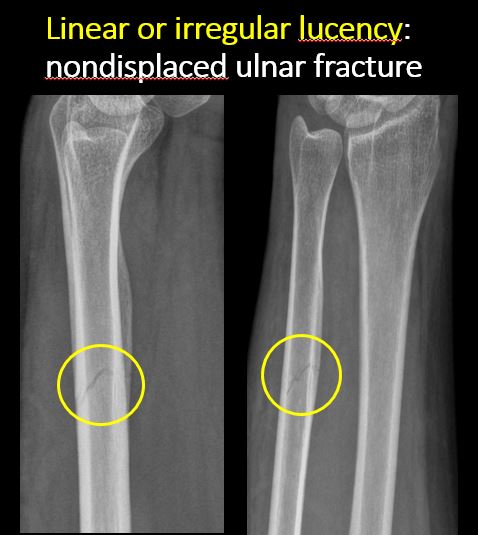

There is linear or irregular lucency, or increased density, cortical depression, flattening, or collapse with or without cortical disruption or thickening, which may be from a compression or impaction fracture, stress or insufficiency fracture, osteonecrosis, or other fracture. |

Yes | NA |